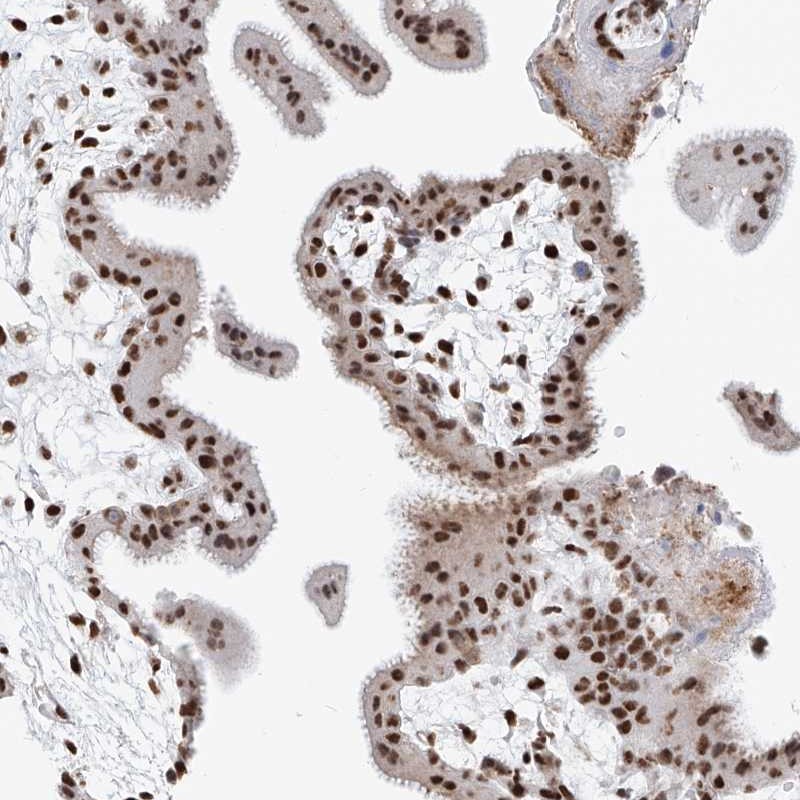

Immunohistochemical staining of human placenta shows strong nuclear positivity in trophoblastic cells.